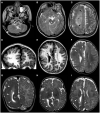

Macrocephaly affects up to 5% of the pediatric population and is defined as an abnormally large head with an occipitofrontal circumference (OFC) >2 standard deviations (SD) above the mean for a given age and sex. Taking into account that about 2-3% of the healthy population has an OFC between 2 and 3 SD, macrocephaly is considered as "clinically relevant" when OFC is above 3 SD. This implies the urgent need for a diagnostic workflow to use in the clinical setting to dissect the several causes of increased OFC, from the benign form of familial macrocephaly and the Benign enlargement of subarachnoid spaces (BESS) to many pathological conditions, including genetic disorders. Moreover, macrocephaly should be differentiated by megalencephaly (MEG), which refers exclusively to brain overgrowth, exceeding twice the SD (3SD-"clinically relevant" megalencephaly). While macrocephaly can be isolated and benign or may be the first indication of an underlying congenital, genetic, or acquired disorder, megalencephaly is most likely due to a genetic cause. Apart from the head size evaluation, a detailed family and personal history, neuroimaging, and a careful clinical evaluation are crucial to reach the correct diagnosis. In this review, we seek to underline the clinical aspects of macrocephaly and megalencephaly, emphasizing the main differential diagnosis with a major focus on common genetic disorders. We thus provide a clinico-radiological algorithm to guide pediatricians in the assessment of children with macrocephaly.